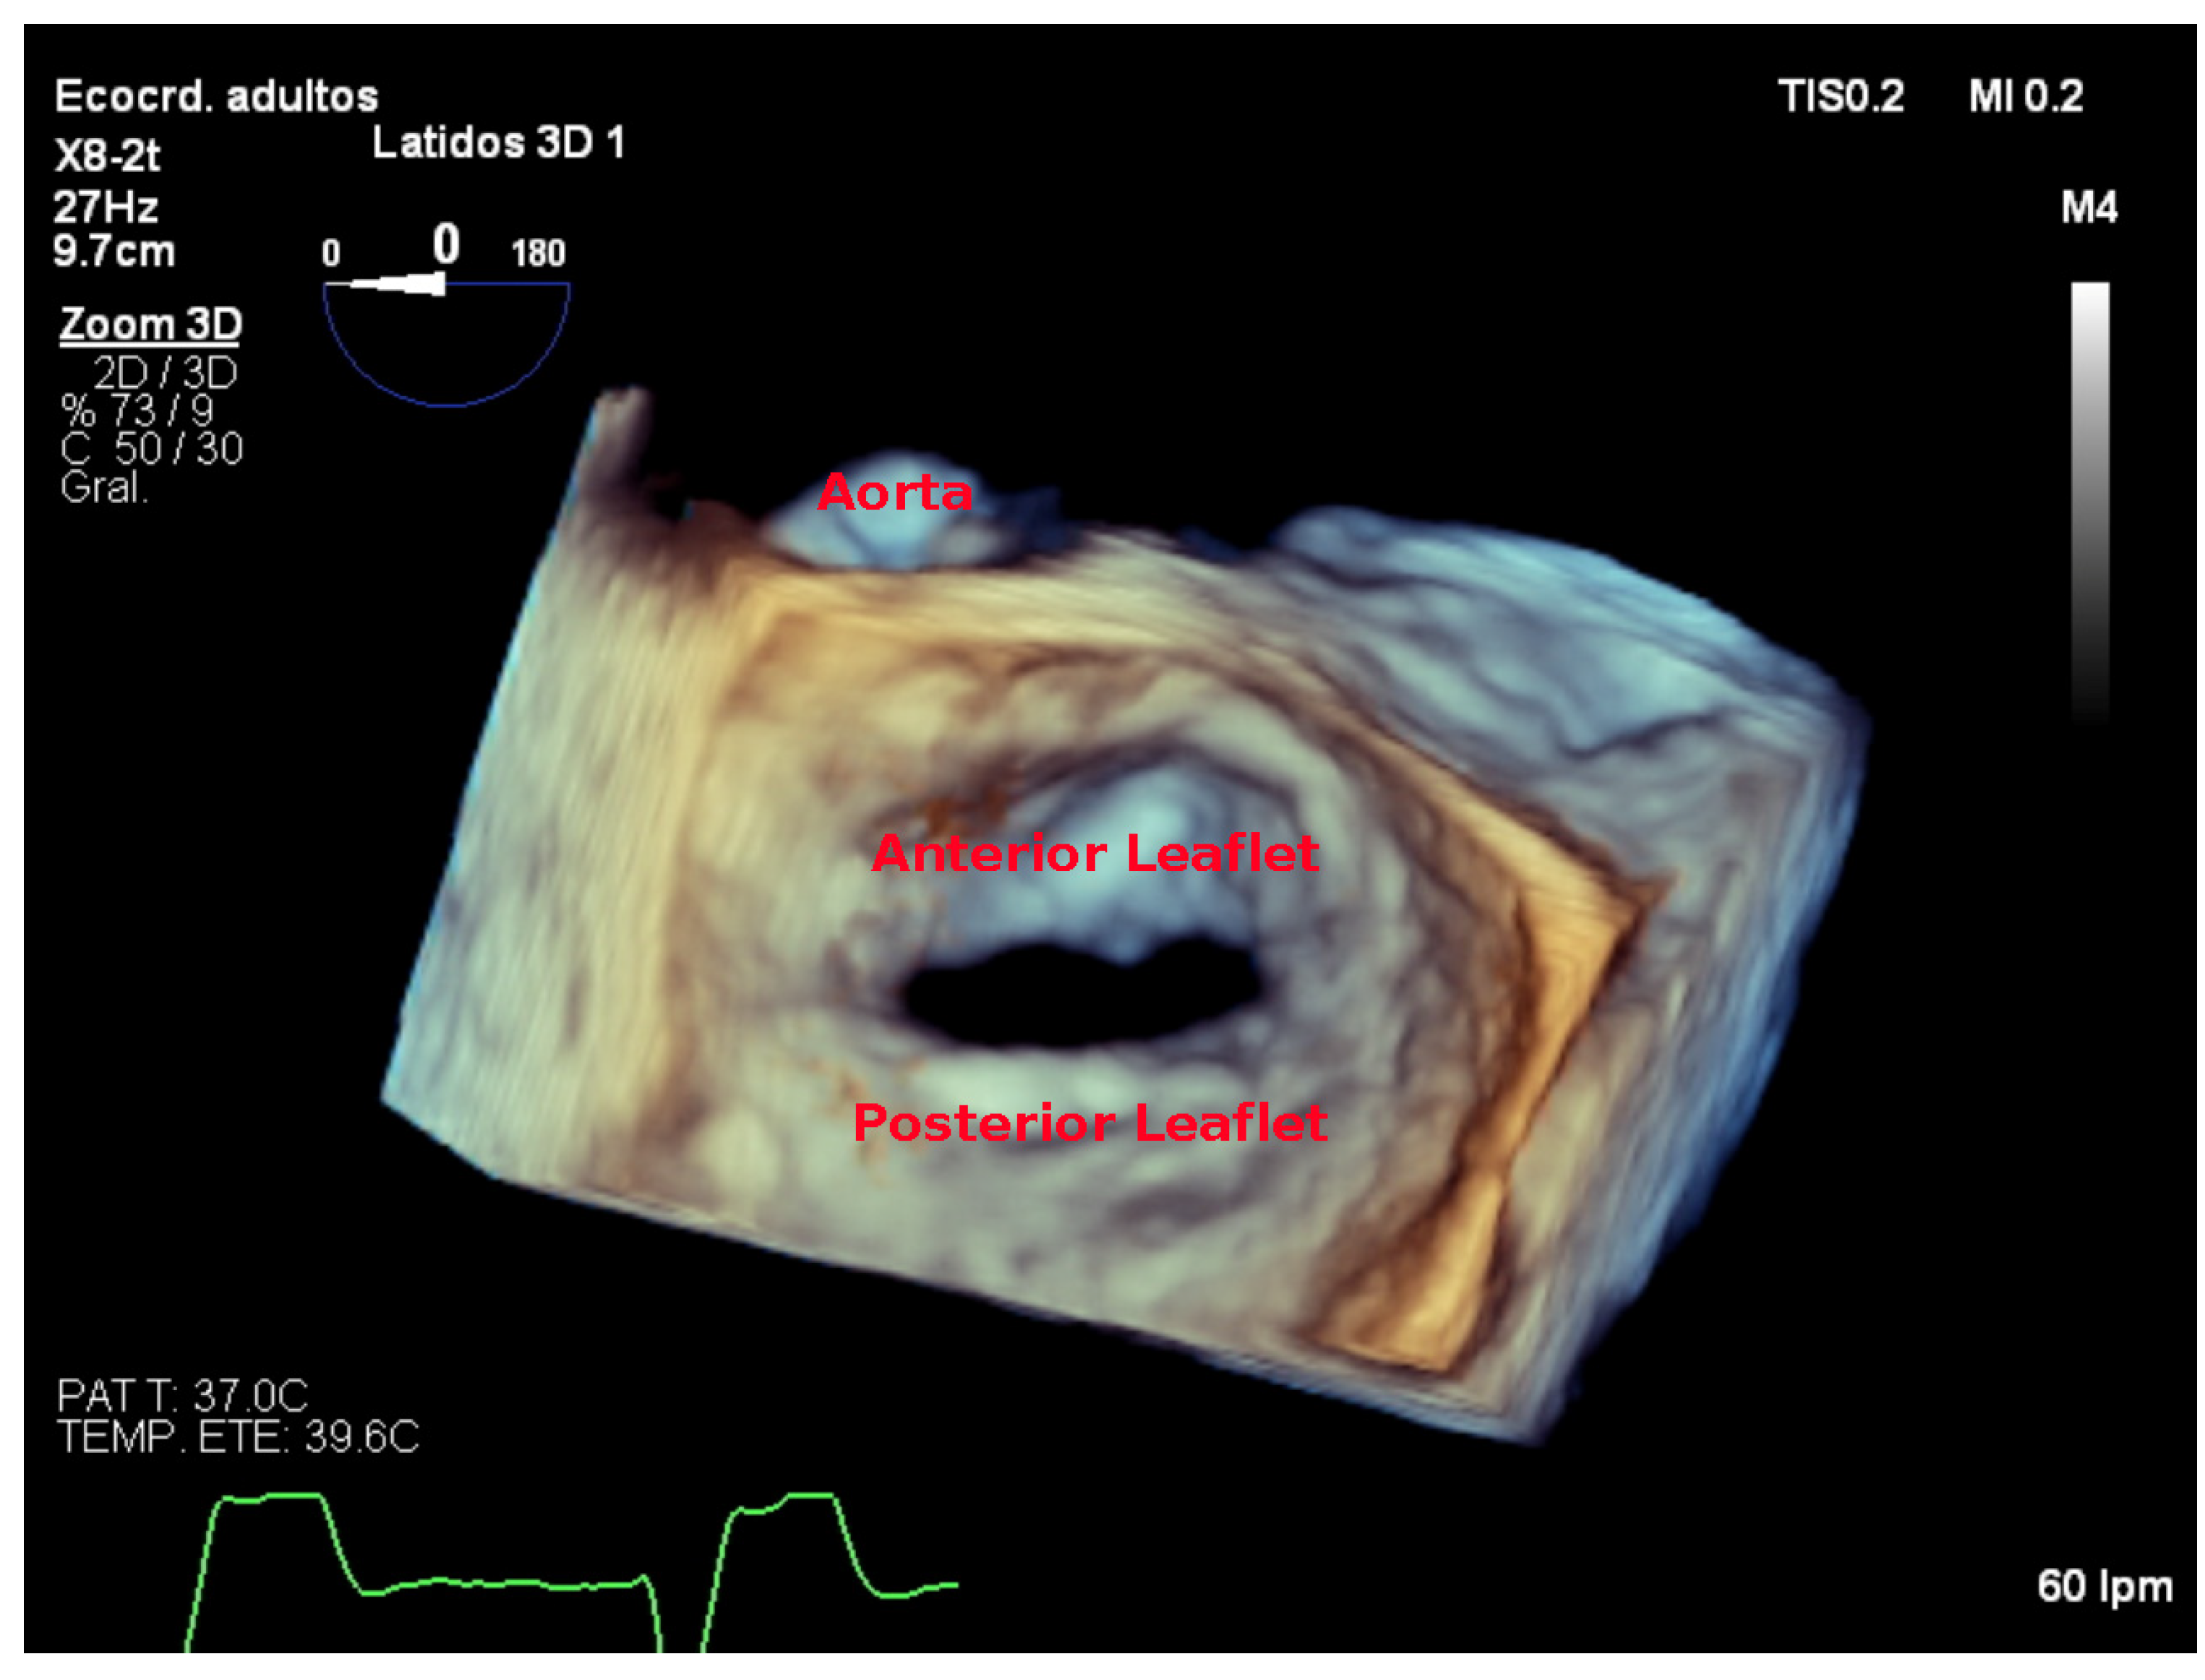

7.4. Focused Wide-Sector (3D Zoom) Imaging